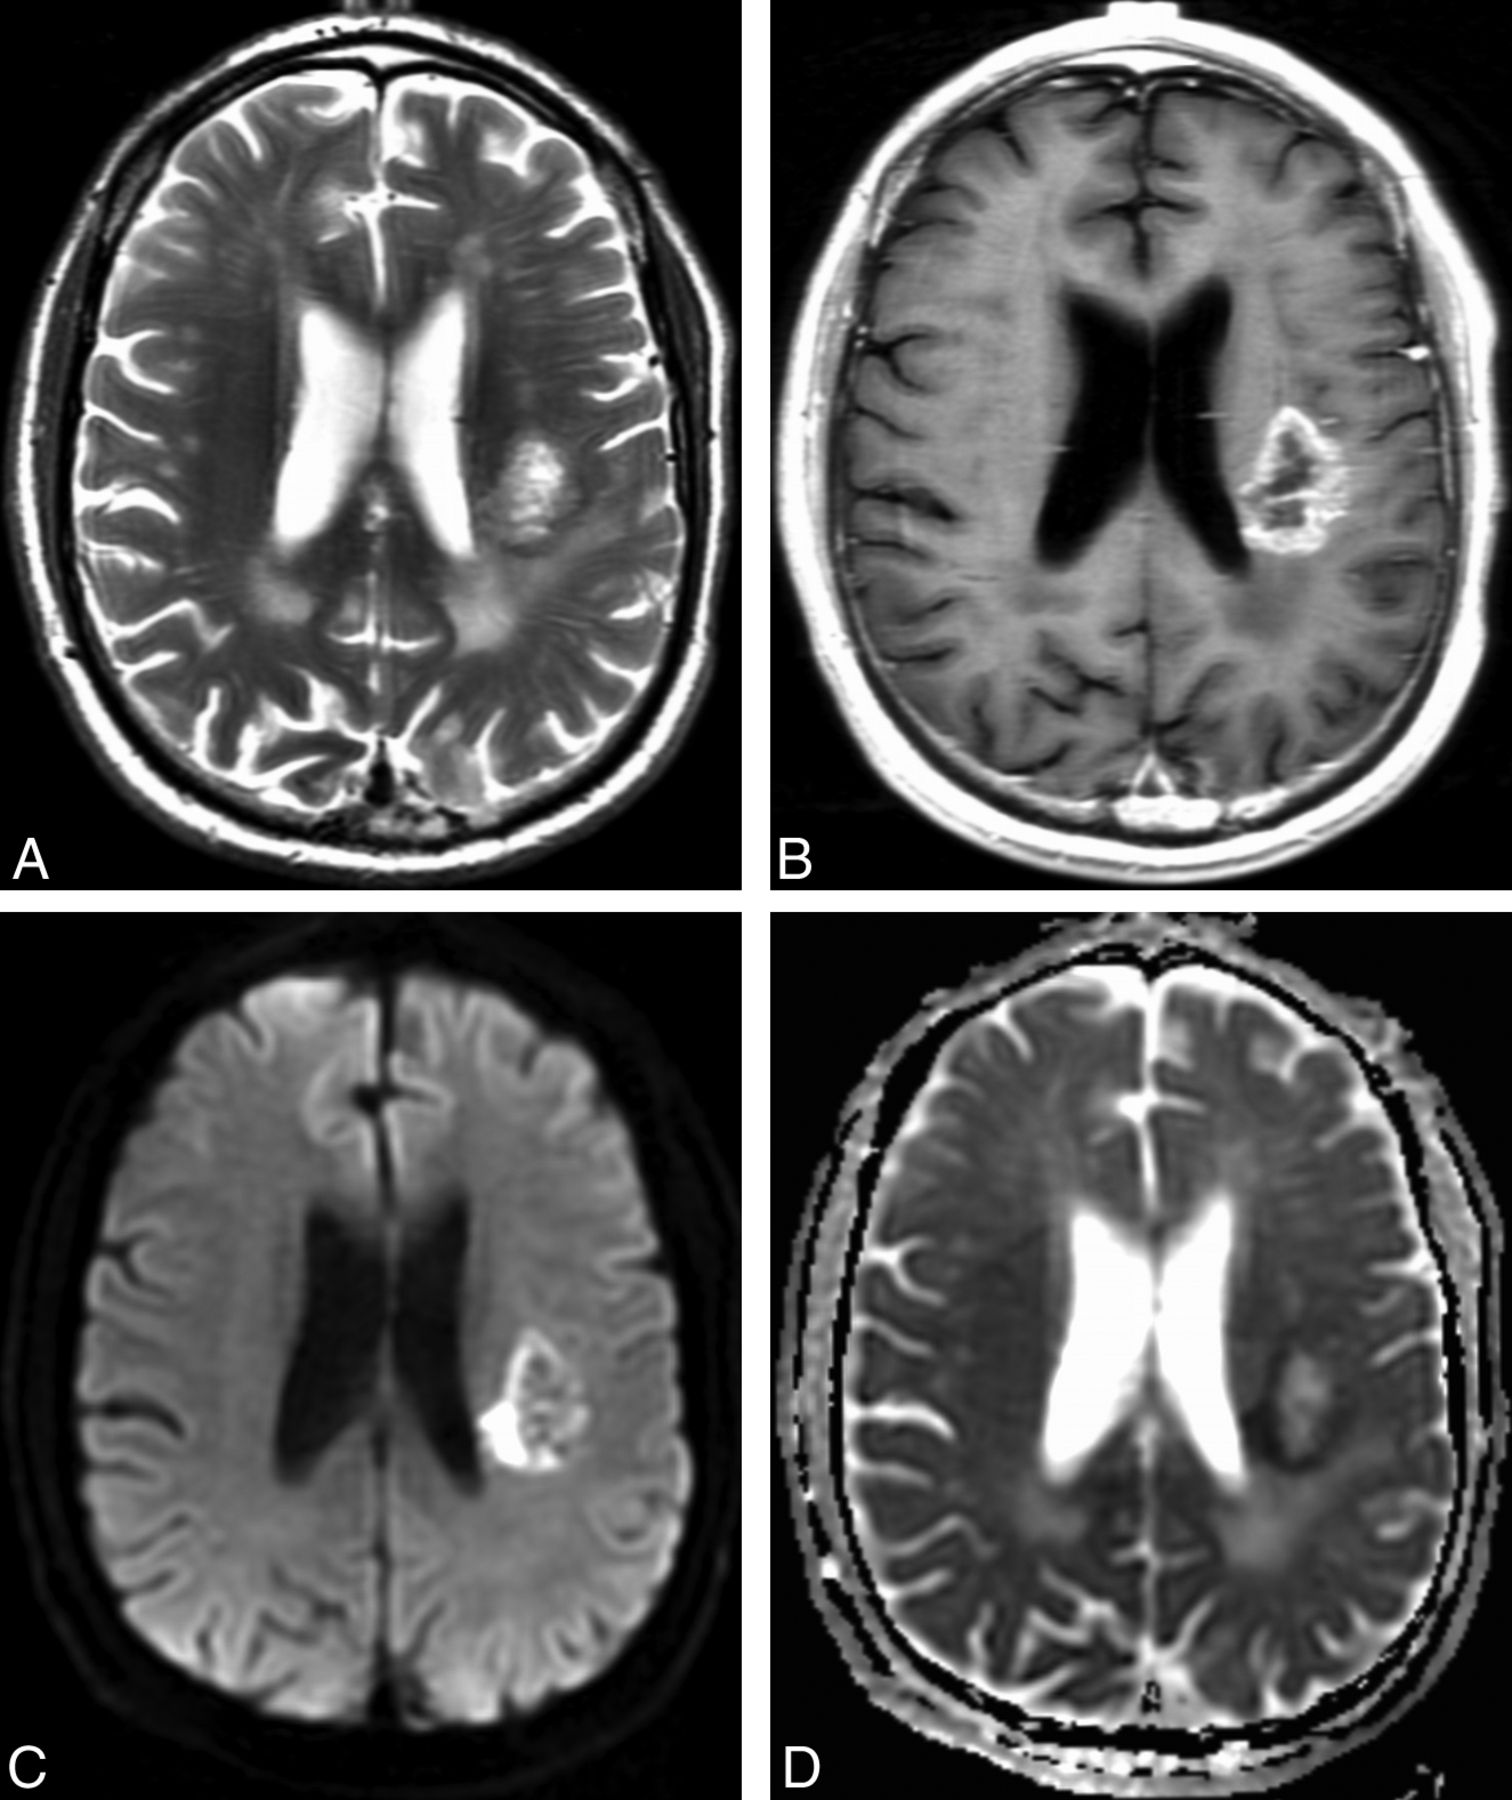

The morphologic MR imaging results are summarized in Table 2. All patients in the cohort had preoperative morphologic MR imaging available for qualitative analysis. Restricted water diffusion occurred in 37% of patients with EGFR amplification and in 21% of patients without EGFR amplification (P = .04). A representative case is shown in Fig 2. The related sensitivity (36.7%; 95% CI, 24.9%–50.2%) and specificity (79.1; 95% CI, 68.7%–86.8%), however, were moderate with area under the curve for the receiver operating characteristic curve = 0.579. The remaining 7 morphologic MR imaging signs were not significant (P > .12).

Representative example of restricted water diffusion in an EGFR-amplified tumor. Axial T2-weighted (A) and contrast T1-weighted (B) images show a heterogeneously enhancing glioblastoma in the left posterior corona radiata. DWI (C) shows hyperintense peripheral restricted water diffusion that is confirmed on the ADC image (D) with a hypointense signal, and corresponds to the enhancing fraction seen in (B). ADCmean measurement of the enhancing fraction was 0.13 × 10−3 mm2/s. Fluorescence in situ hybridization analysis revealed high-level EGFR amplification with 98% of 200 analyzed cells showing > 20 signals for EGFR.